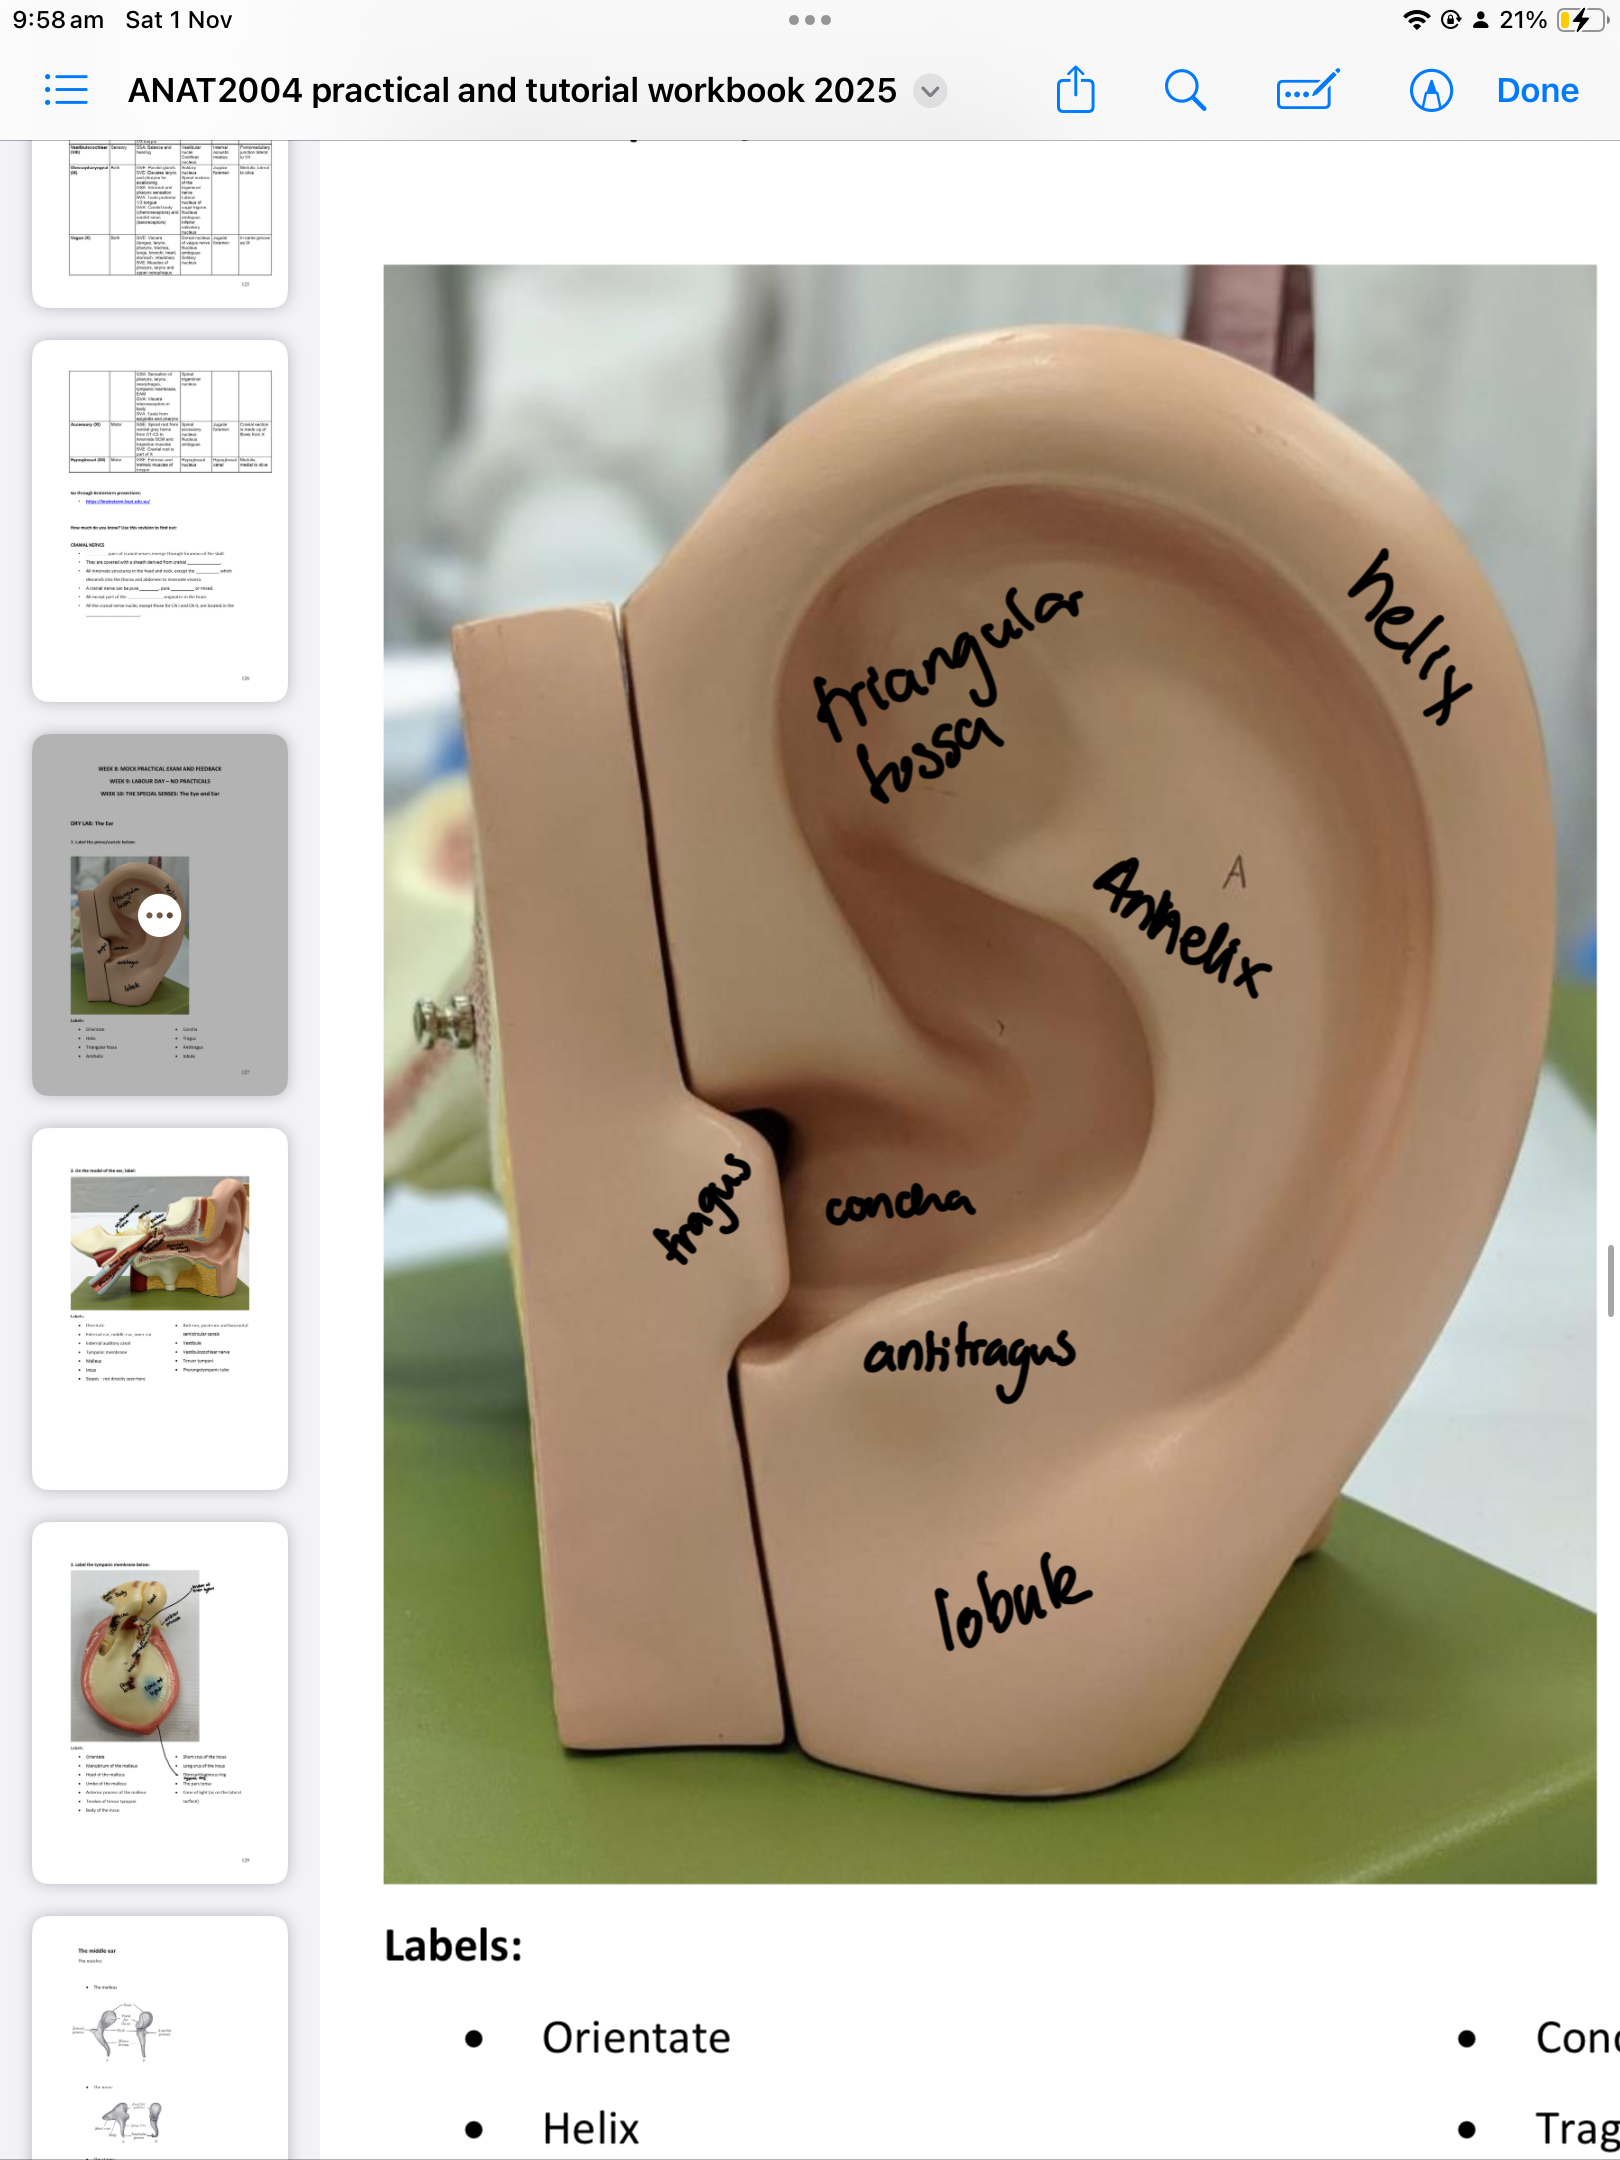

The Outer Ear

Helix

Triangular fossa

Antihelix

Concha

Tragus

Antitragus

Lobule